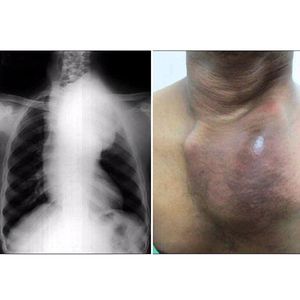

This patient presented with a large pulsatile swelling of 4 months' duration on the left side of the chest. Initially, he noticed a small 4 × 4 cm swelling below the left clavicular region, which rapidly increased in size to about 10 × 10 cm in 4 months. He complained about breathlessness. No history of trauma. Local examination (right figure) showed a large swelling on the left side of the anterior chest wall. Chest roentgenogram (left) showing widening of the mediastinum with a radiopaque mass extending into the superior mediastinum occupying the left upper and mid-zone with a right tracheal shift. His blood serology was positive for syphilis and hepatitis B surface antigen. The patient was immediately admitted to the cardiothoracic surgery division for management.